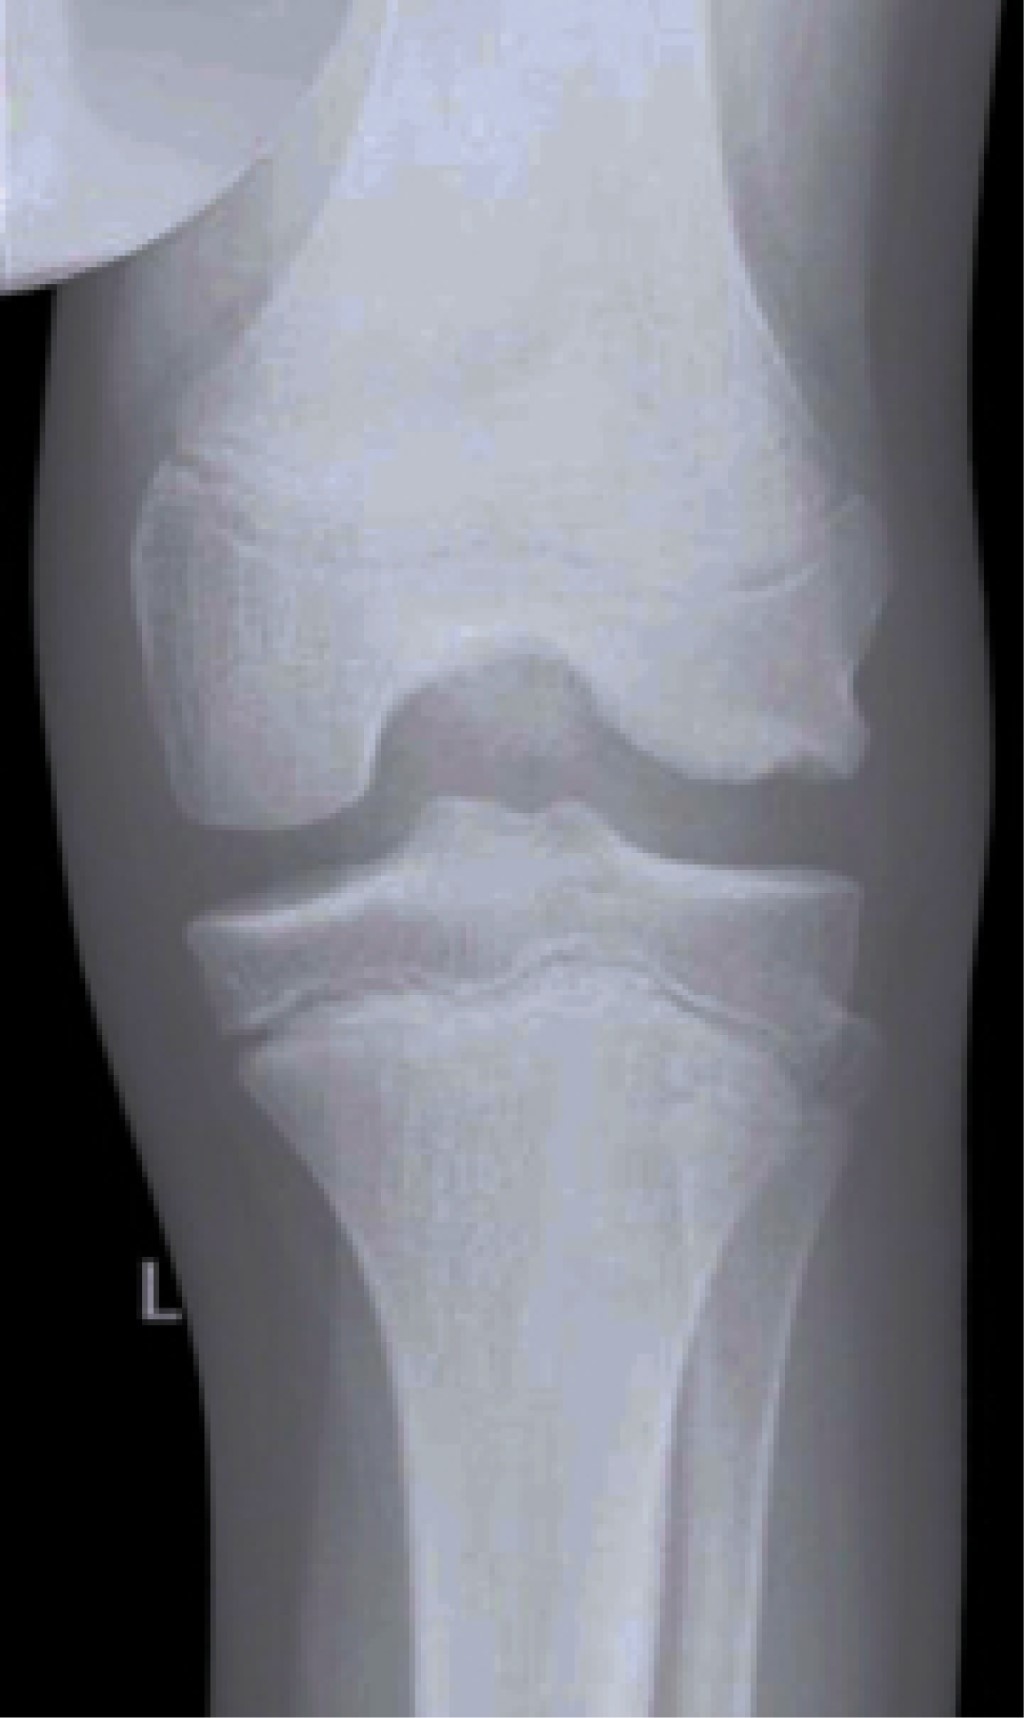

RADIOGRAFíAS SIMPLES

Se deben obtener radiografías simples de la rodilla en todos los pacientes; incluyendo la proyección anteroposterior, lateral, de túnel y de Merchant.

Las imágenes suelen ser normales y se utilizan para descartar otras patologías; cuando encontramos alteraciones compatibles con menisco discoide, se trata de una patología avanzada.64

Los signos radiográficos más frecuentes son: aumento del espacio articular lateral (hasta 11 mm), aumento de la altura de la cabeza del peroné, hipoplasia de la espina tibial lateral, oblicuidad de la meseta tibial lateral, apariencia cuadrada del cóndilo femoral lateral, ahuecamiento de la meseta tibial lateral y el condylar cutoff sign en la proyección de túnel (Figura 3).65-67